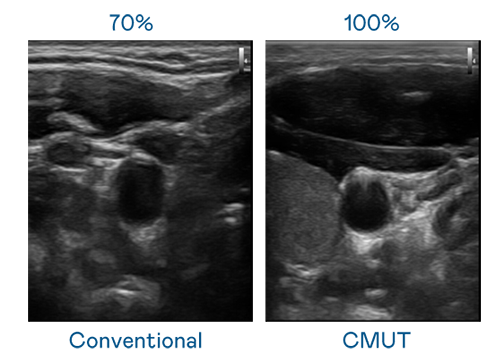

CMUT 技术是一种用电容式微机电元件来产生超音波讯号的技术。与传统 PZT 压电式技术相比,CMUT 频宽增加 30%,更宽频的超音波讯号让影像解析度大幅提升,是实现高影像品质医疗超音波扫描、促进精准医疗发展的关键技术。

大频宽带来超清晰影像

超音波影像的解析度高低,首先取决于探头能发出的讯号频宽。pg电子 CMUT 可提供高清晰的超音波讯号,提供高频宽、高灵敏度、影像纹理细节更高的超音波影像,协助医护人员缩短影像判读时间及利用精准的医疗影像进行诊断。